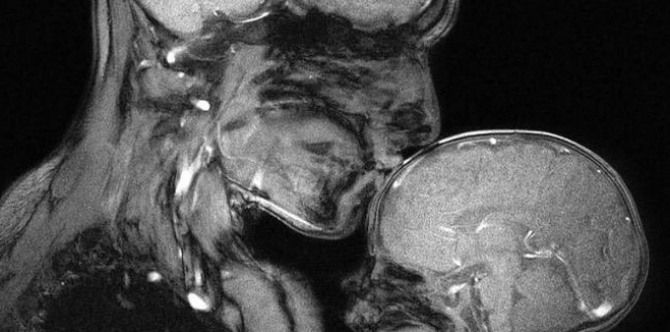

Look: A mother’s love for her child, caught in an MRI scan

Read on to find out the touching story behind this amazing photo!

MRI scans are usually used to capture images of the human body that helps diagnose and treat a person’s illness. But in this case, a mother’s love for her child was capture by an MRI scan.

After Neuroscientist Rebecca Sax gave birth to her first child, she fell in love with the idea of watching her child’s brain develop. She spent countless hours in an MRI scanner with her son, observing how his brain was growing along with his body. (Note: MRI scanners don’t produce any radiation, and they are perfectly safe for children)

Eventually, her fascination with seeing her child’s growth and development led into the idea of taking an MRI scan of her and her baby together.

According to Rebecca, taking the image was difficult, since the scanner she used was made for taking MRI scans of a single person. It took numerous modifications as well as months of working with medical technicians before the scanner was modified to take a scan of her and her baby.

And on April 2015, after giving birth to her 2nd baby, she was finally able to take the amazing image.

She shares, “It’s very, very hard to make. You have to hold still for a few minutes to get the picture. Try to convince a little baby to lie [still].”

MRI machines are also noisy, so to help keep her child from moving around too much or being scared of the noise, her baby had to wear pads over his ears. She in turn had to wear earplugs herself.

After a couple of hours and 25 attempts, they finally got the scan that the wanted.

“I thought they were beautiful. I couldn’t take my eyes off them,” Rebecca shares.